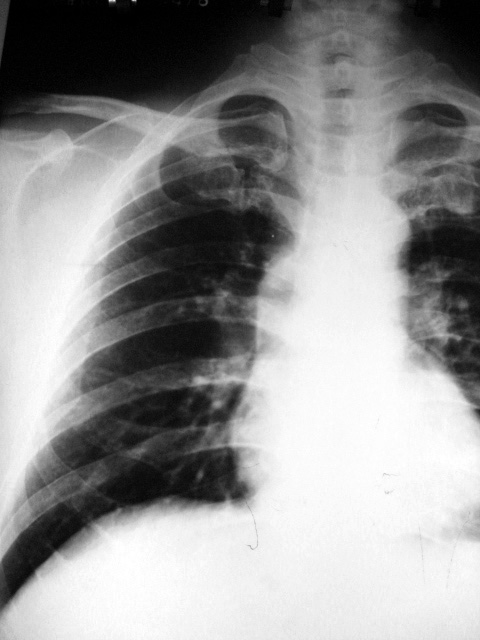

标题: X4751:M56Y,胸片会诊

男,56岁,体检。

纵隔占位性病变可能性大,建议ct进一步检查。

考虑纵隔占位可能。作进一步检查。

迂曲的主动脉

考虑纵隔占位性病变,建议ct进一步检查

接上面内容,考虑升主动脉迂曲。

考虑升主动脉投影所致。

应该有个侧位 ,首先考虑迂曲的主动脉,不放心的话就做ct .

考虑纵隔占位性病变可能大,建议ct进一步检查。

首先考虑迂曲的主动脉,其次考虑纵隔占位,加个侧位看看